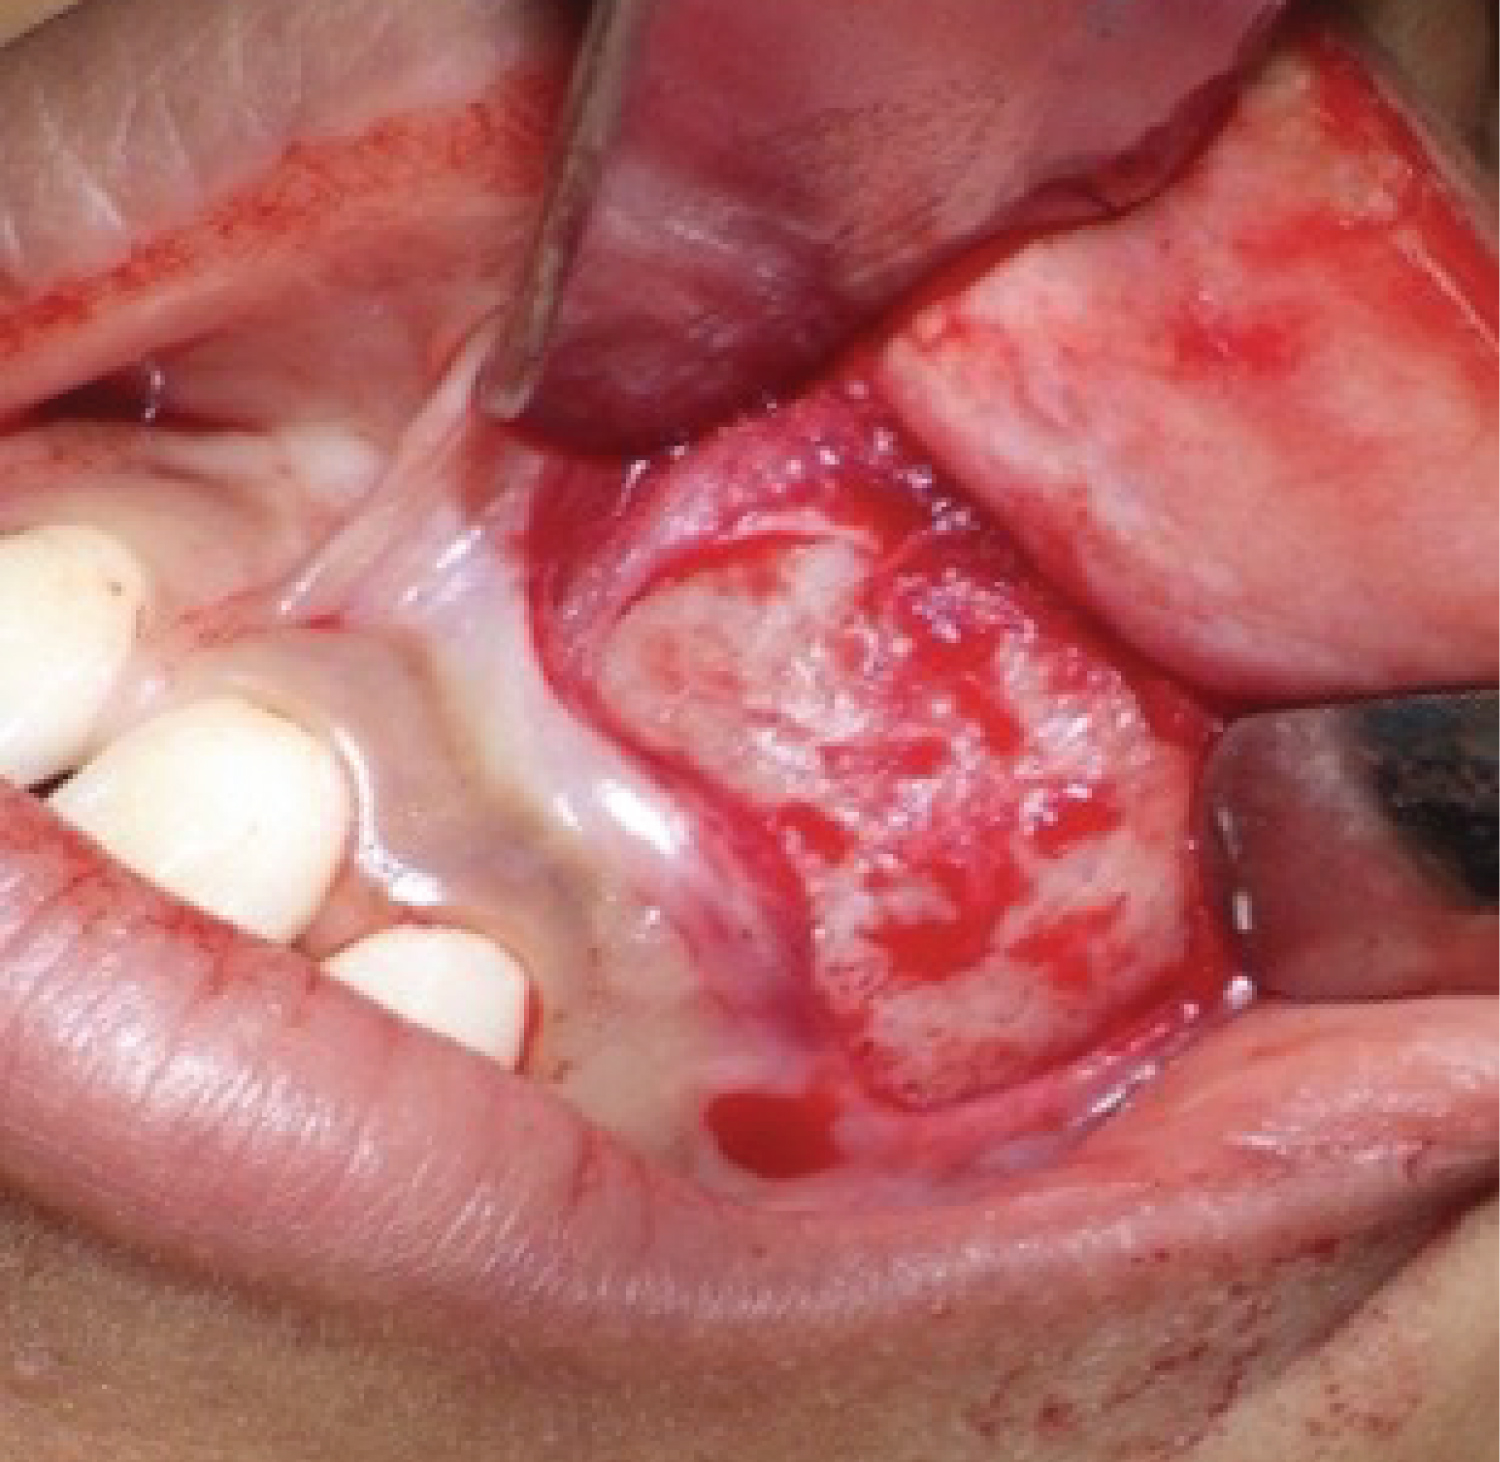

The treatment, initially, consisted of an incisional biopsy which histopathologic study reported the definitive diagnosis of Adenomatoid Odontogenic Tumor. Posteriorly, under general anesthesia, enucleation and curettage was performed as definitive treatment (Figure 2 and Figure 3).

Figure 2: Tumor exposure through vestibular incision. View Figure 2

Figure 3: Enucleationy curettage. View Figure 3